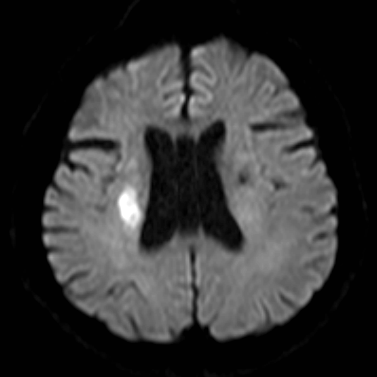

脑梗塞

新鲜脑梗塞

右侧MCA长节段血管变细狭长